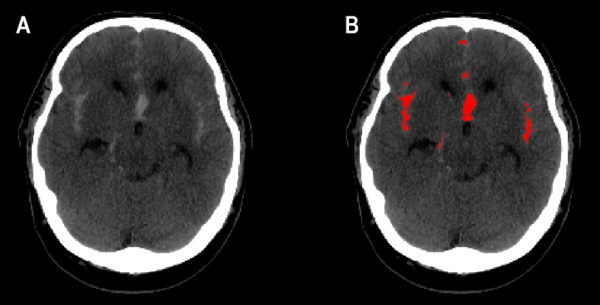

Subarachnoid hemorrhage (SAH) is a life-threatening cerebrovascular disorder where the rupture of a bulging blood vessel, called an aneurysm, causes bleeding in the brain.